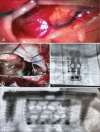

Figure 5:

Direct occlusion of the low cervical, ventral, spinal dural fistula. (a) shows anterior cervical approach, and (b) shows the C5 corpectomy. In postoperative anteroposterior (c) and lateral (d) X-ray views, the interbody spacer and the anterior lordotic plate are seen.